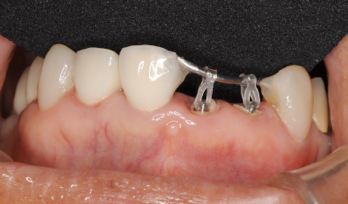

歯が1ヶ月くらいで出てきますが、歯茎もいっしょに出てくるので、余分な歯茎を取り除きます

歯茎から歯が出ました